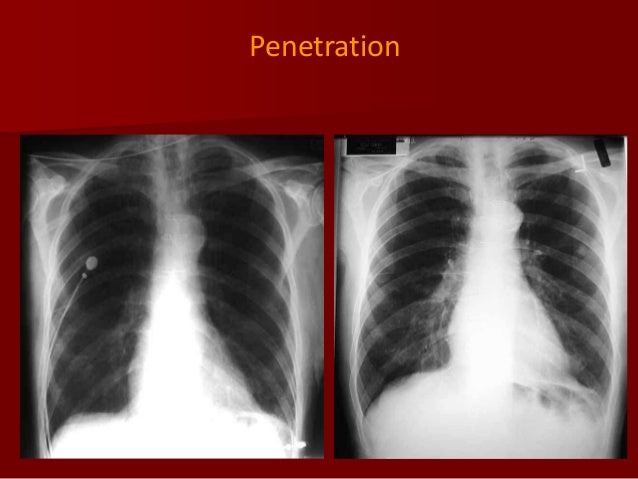

The image has been acquired by a mobile x ray unit in the resuscitation room. There appears to be a bilateral interstitial infiltrate also due to underinflation. The superior mediastinum appears widened due to ap magnification. This distance diminishes the effect of beam divergence and magnification of structures closer to the x ray tube.

Ap projection images are of lower quality than pa images. Compare this image with the pa view below. Ap projection example. Clavicle remains at top of lung field 2.

The heart appears enlarged a combination of ap magnification and underinflation. Heart shadow looks larger 5. Like all methods of radiography chest radiography employs ionizing radiation in the form of x rays to generate images of the chest. A chest radiograph called a chest x ray cxr or chest film is a projection radiograph of the chest used to diagnose conditions affecting the chest its contents and nearby structures.